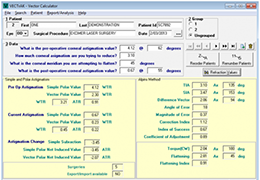

Designed for surgeons, Pro Surgical 3D makes it easy to view patient scans quickly. Pro Surgical 3D facilitates the optimal 3D treatment and assessment workflows based on X-ray CT and MRI scans – and best of all, it’s FREE!

Everyone – including surgeons, patients and their loved ones – benefits from being better informed by the wealth of information buried within CT and MRI scans. Pro Surgical 3D gives surgeons more information to develop optimal treatment plans for patients. It also helps patients and their support group better understand their medical condition and proposed treatment options.